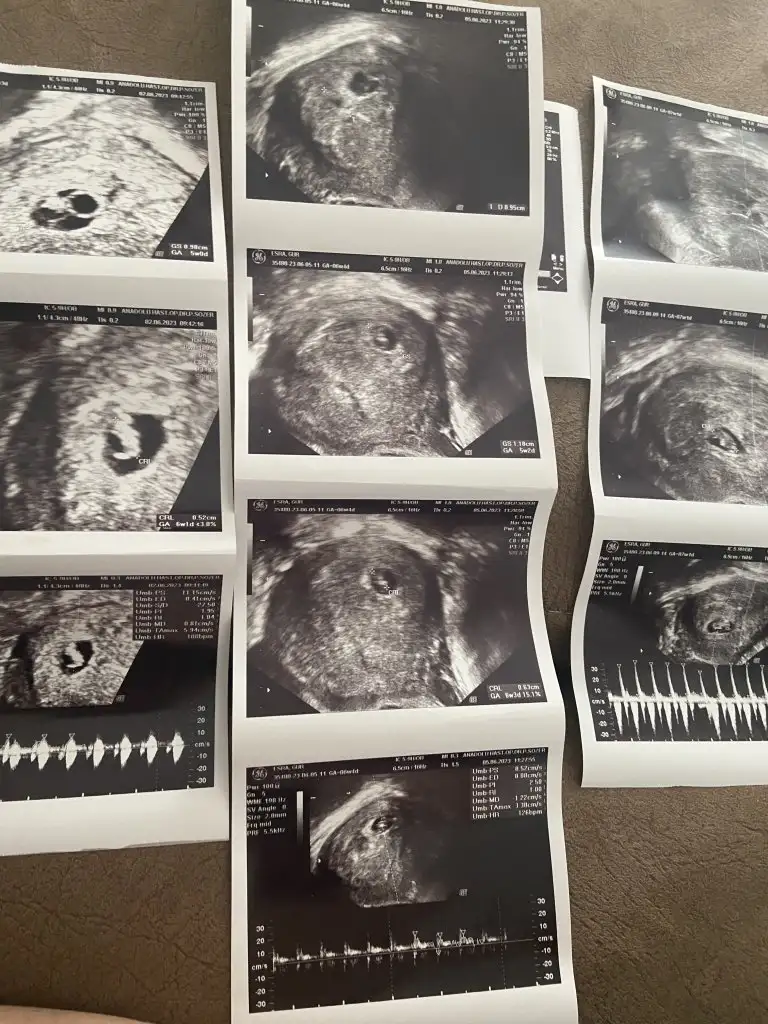

Cumartesi gidecem hafta dolmadan gidiyorum zaten mayıs sonundan beri kese 6+0 bebek 7+0 çıktı en son dr düzelir diye rahatlatmaya çalışıyor ama yine de hep tedirginim lekelenmemde var 10-15 gündür zaten farkın kapanmasını bekliyorum